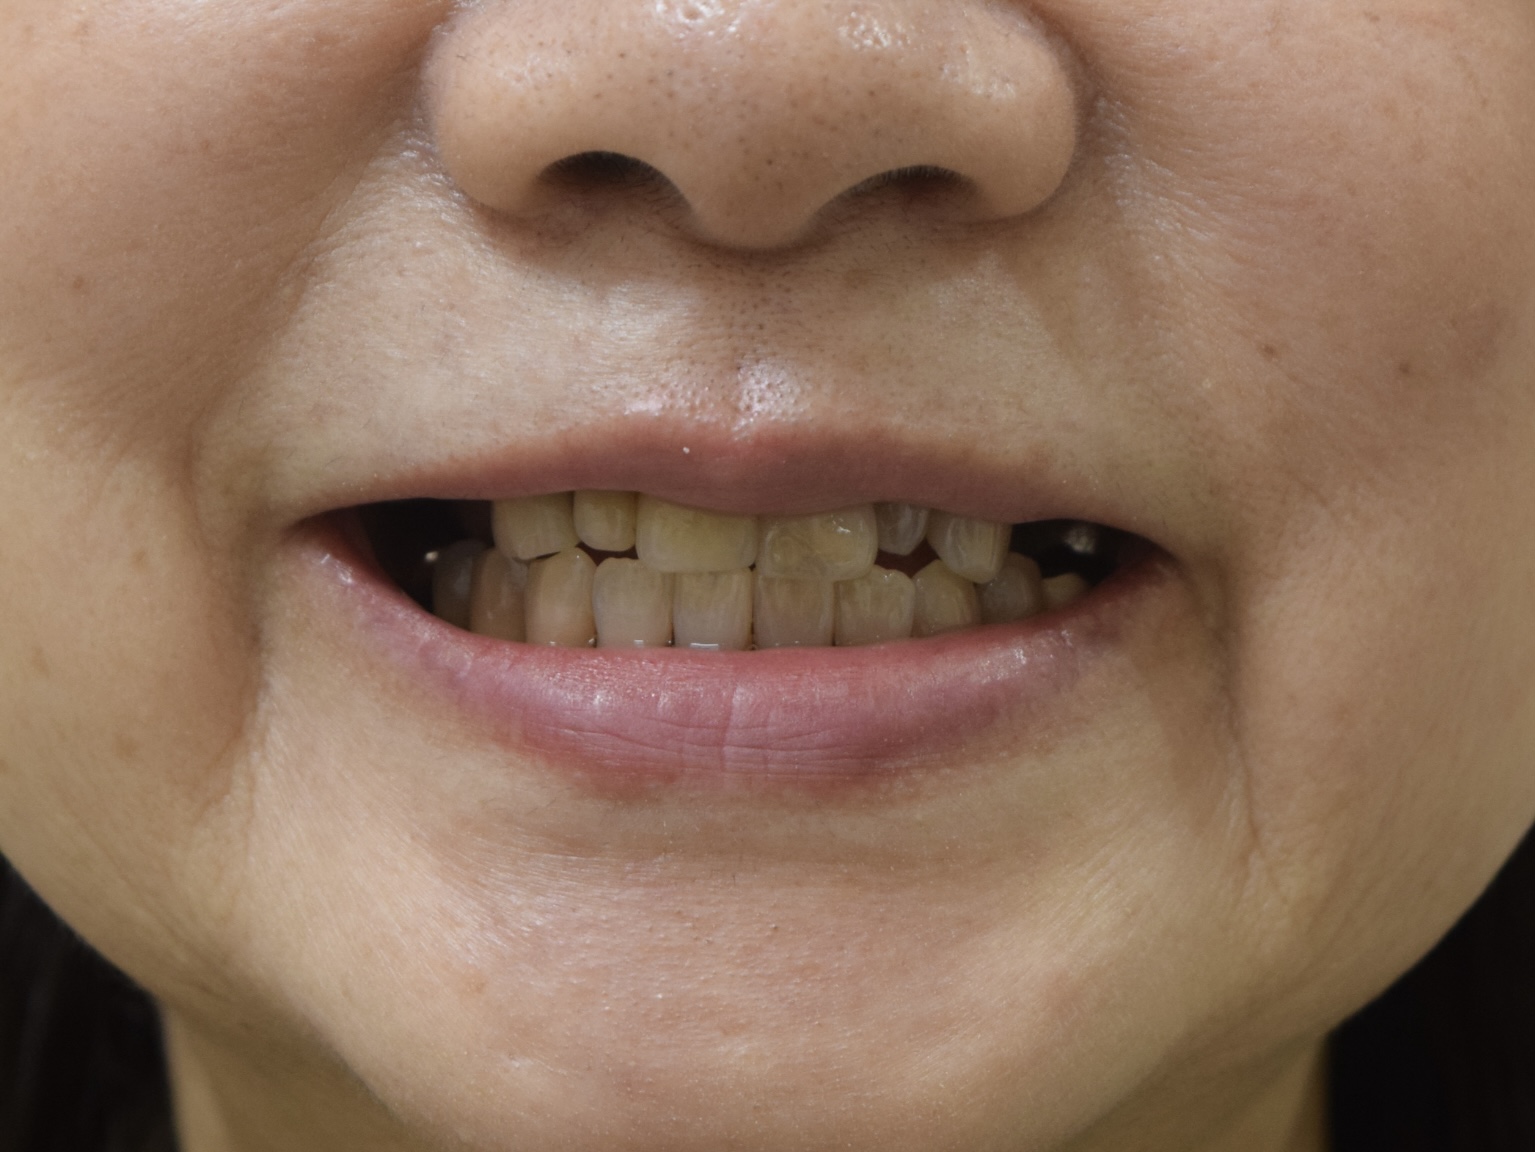

ご来院の動機